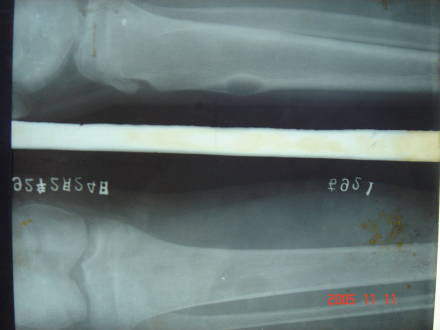

1.X线检查病变发生于骨干或近干骺端一侧皮质骨内,不累及骨骺,病灶呈偏心性膨胀性改变,多为不规则的单囊或多囊形,轮廓清晰,边缘硬化,病变一般不穿破骨皮质,无骨膜反应。病变范围广泛者,可致患骨明显畸形。

2.CT检查 可见骨皮质内囊状破坏,其间常有增生骨化所致的不规则高密度区,硬化成骨区的CT值500~1400Hu不等,骨皮质不规则增厚,向髓腔内突出致髓腔变形、变小,有时可致髓腔闭塞。